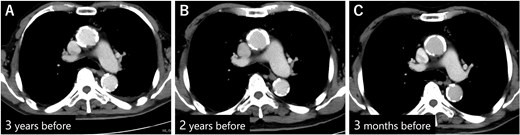

Postoperatively, we obtained additional information about the patient’s medical history. The patient had been bedridden for ~5 years due to severe dementia and required total assistance. A family member, who had a clinical nurse license, monitored medication use and daily blood pressure, which was stable; moreover, the patient’s antihypertensive drug had not been changed for a long time. Because the patient had a history of percutaneous coronary intervention at another hospital, the patient had undergone coronary computed tomography angiography follow-up. The images revealed that the maximum diameter of the descending aorta was 28 mm, and although arteriosclerotic changes were significant, the diameter had not changed for at least 3 years (Fig. 3A–C). The patient had long-term use of a urinary catheter for benign prostatic hypertrophy; therefore, the patient repeatedly developed UTIs and was treated with LVFX in almost all cases. In particular, 7 months before presentation, the patient received LVFX prescription four times, for 39 days in total (Fig. 4).

(A) CECT 3 years before presentation showed that the diameter of the descending aorta was 28 mm. (B) CECT 2 years before presentation. (C) CECT 3 months before presentation. Diameter of the descending aorta was unchanged during that period.